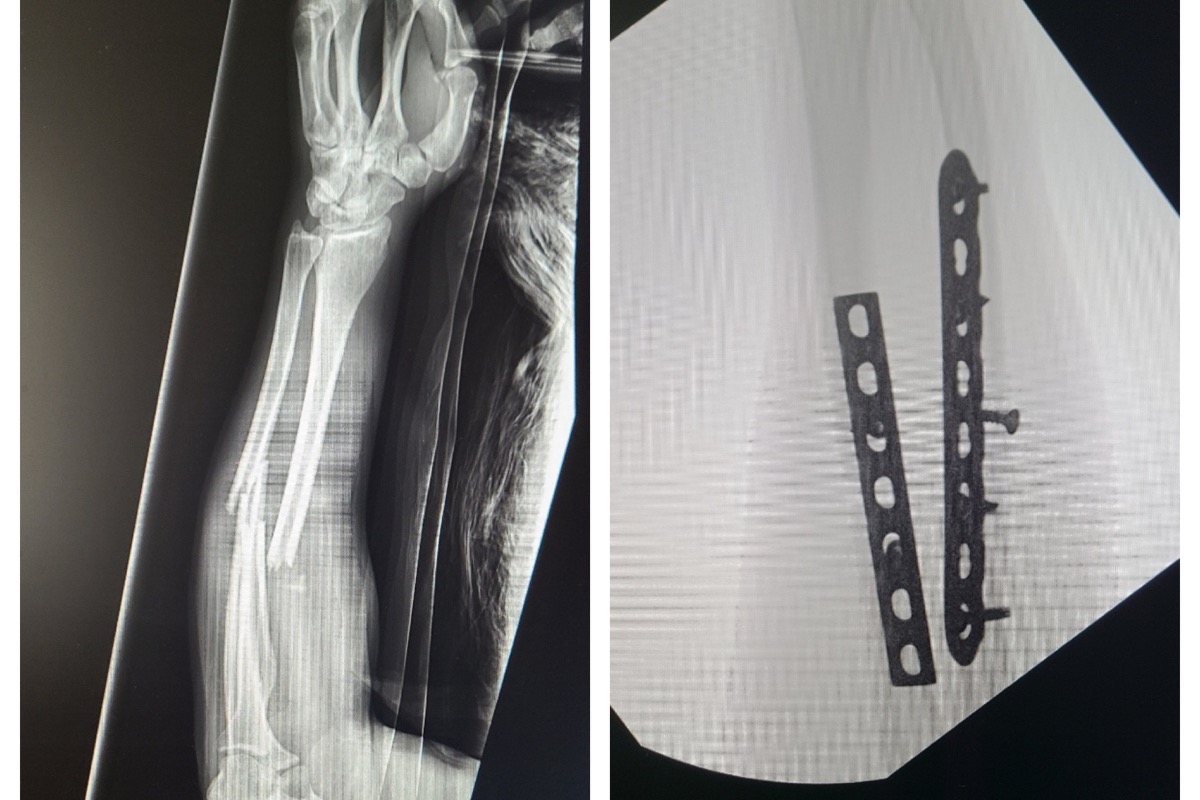

Unfortunately, two nights ago (February 8th, around 9 pm) while skating at a skate park in Linda Vista, she took an awkward fall and broke both bones in her right forearm. She is now hospitalized and under pain management due to the severity of the break. She went into surgery last night and is now recovering in the hospital before being released. Samantha is uninsured, and the cost of this accident will be crippling for her.